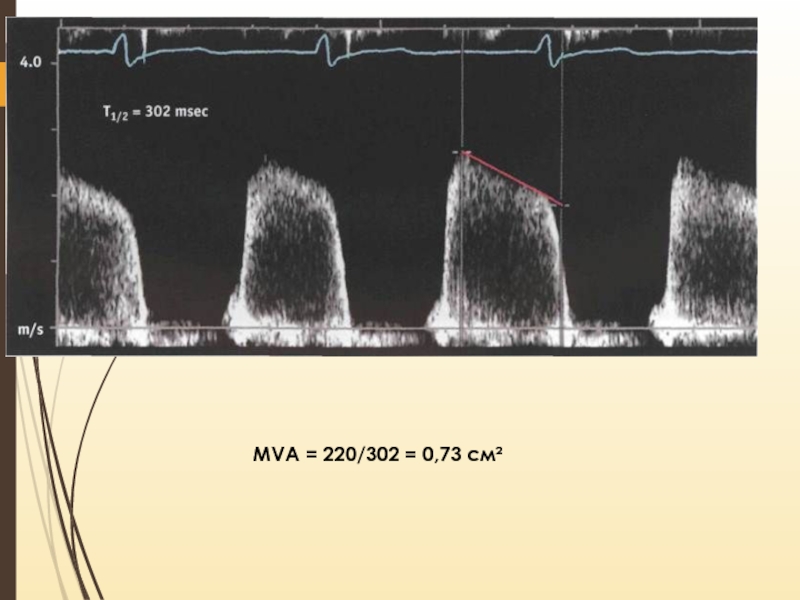

Слайд 17Доплеровские измерения

Время полуспада градиента давления (T 1/2) – время, за

которое максимальный градиент давления между левым предсердием и желудочком снизится

вдвое

Градиент давления пропорционален квадрату скорости кровотока (ΔP = 4V2) => время полуспада давления равно времени, за которое максимальная скорость снижается в √2 (около 1,4)

Хатле и соавт. установили, что T 1/2 = 220 мс соответствует MVA = 1 см2 => существует линейная зависимость между T 1/2 и MVA

Измерение в ПВ – режиме в 4-камерной позиции из апикального доступа

Слайд 18MVA = 220/302 = 0,73 см²

MVA = 220/302 = 0,73 см²